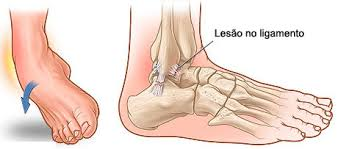

Anatomia dos Ligamentos do Tornozelo

O tornozelo é sustentado por um conjunto de ligamentos que desempenham um papel crucial na estabilidade e mobilidade da articulação.

Esses ligamentos conectam os ossos do tornozelo entre si e impedem movimentos excessivos que poderiam causar lesões.

Os principais ligamentos do tornozelo incluem:

Ligamento Talofibular Anterior (LFTA): Este é o ligamento mais comumente lesionado durante uma entorse. Ele conecta o osso tálus ao osso da fíbula e é responsável por limitar a rotação interna do tornozelo.

Ligamento Calcaneofibular (LCF): Localizado abaixo do LFTA, este ligamento conecta o calcâneo (osso do calcanhar) à fíbula e ajuda a prevenir a inversão excessiva do pé.

Ligamento Talofibular Posterior (LFTP): Este ligamento conecta a parte posterior do talus à fíbula e é menos frequentemente lesionado, mas ainda desempenha um papel importante na estabilidade do tornozelo.

Ligamentos Mediais ou Deltoide: Localizados na parte interna do tornozelo, esses ligamentos são mais fortes e menos propensos a lesões, mas ainda podem ser afetados em entorses graves.

Mecanismos de Trauma do entorse de tornozelo

A entorse de tornozelo geralmente ocorre devido a um movimento brusco ou inadequado que força o tornozelo além de sua amplitude normal de movimento.

Os mecanismos de trauma mais comuns incluem:

Torção: Um movimento de torção ou rotação do pé enquanto ele está preso no chão pode causar uma entorse.

- Inversão: Este é o mecanismo mais frequente, onde o pé gira para dentro, forçando os ligamentos laterais (especialmente o LFTA) a se esticarem ou rasgarem.

2. Eversão: Menos comum, ocorre quando o pé gira para fora, podendo lesionar os ligamentos mediais.

Impacto direto: Apesar de bem menos comum, um golpe direto na parte externa ou interna do tornozelo também pode resultar em lesão ligamentar, especialmente em esportes de contato.